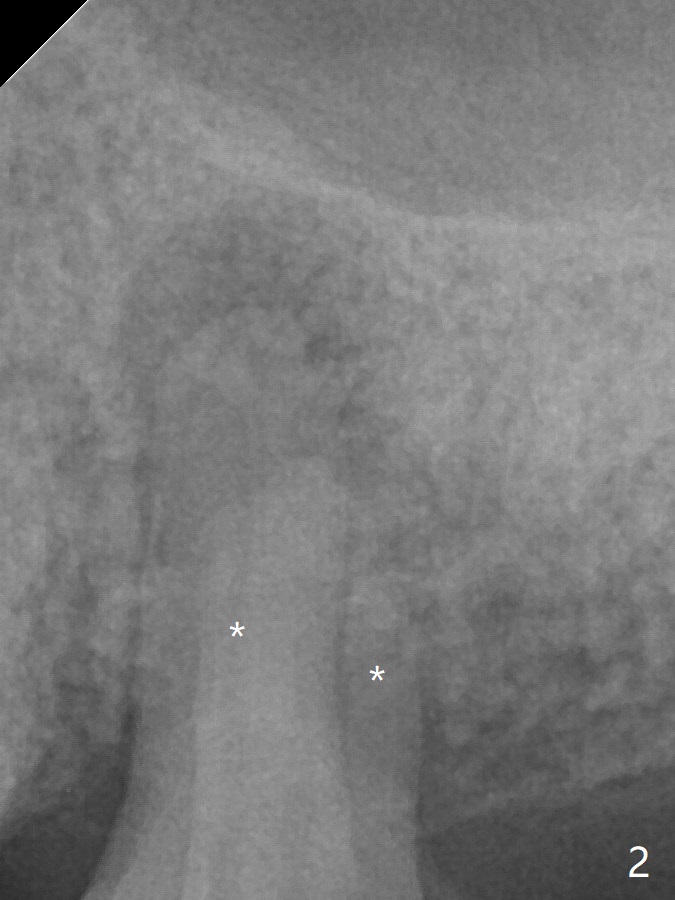

A 59-year-old woman has lost several teeth. The remaining ones are under stress (over-loaded), either severely worn (Fig.1 #31) or fractured (#13). The latter has 2 sockets with severe infection (Fig.2, IS implant). Start osteotomy in the palatal socket. Since the bone height is 11 mm (Fig.3), place PRF and bone graft before a 4x11 mm implant.